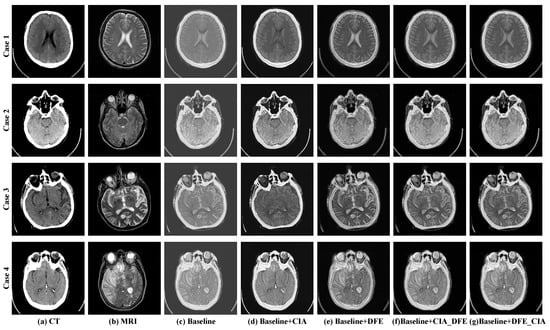

4.3. Ablation Study

To comprehensively evaluate the effectiveness of the proposed DFE and CIA blocks, we conduct a series of ablation experiments with the following detailed network configurations:

- “Baseline” refers to the vanilla generator model without any component.

- “Baseline + DFE” denotes the baseline model with a single DFE block.

- “Baseline + CIA” represents the baseline model with a single CIA block.

- “Baseline + CIA_DFE” refers to the baseline model with the CIA block and DFE block sequentially connected.

- “Baseline + DFE_CIA” refers to the baseline model with the DFE block and CIA block sequentially connected.

The objective comparison results are shown in Table 5. The results prove that the DFE block and CIA block in the generators contribute to substantial improvements in the baseline method. The “Baseline” achieves the lowest performance. Compared with the “Baseline”, the “Baseline + DFE”, and “Baseline + CIA” synergize multi-scale information and salient information, which facilitates an improvement in the objective indicators of the generated images. Specifically, the “Baseline + DFE” achieves 35.5%, 24.9%, 3.8%, and 4.6% improvements in PSNR, SSIM, VIF, and MI, respectively. The “Baseline + CIA” method achieves 31.7%, 18.4%, 4.4%, and 4.6% improvements in PSNR, SSIM, VIF, and MI, respectively. Meanwhile, when the DFE and CIA blocks are simultaneously incorporated into the baseline, the improvement is more obvious. Between these two configurations, the “Baseline + DFE_CIA” is better than “Baseline+CIA_DFE”. The final CFGAN with “Baseline + DFE_CIA” boosts the baseline by 1.3%, 41.2%, 1.6%, 201.2%, 18.1%, and 7.1% in terms of SD, PSNR, CC, SSIM, VIF, and MI, respectively.

The subjective results with different network configurations are illustrated in Figure 12. The example images of four cases are illustrated in Figure 12. Figure 12a,b are the source images of the CT and MRI, respectively. Figure 12c represents the fusion image generated by the baseline method. The CIA block extracts the salient features, including dense structures from CT images and soft tissue detail from MRI images as depicted in Figure 12d. The DFE block can supplement the detailed features of the source image as shown in Figure 12e. Both the compound modes of ‘Baseline + CIA_DFE’ (Figure 12f) and ‘Baseline + DFE_CIA’ (Figure 12g) can preserve more significant information, particularly skull information and details of brain tissue.

Figure 12.

The subjective comparison results of different network configurations.